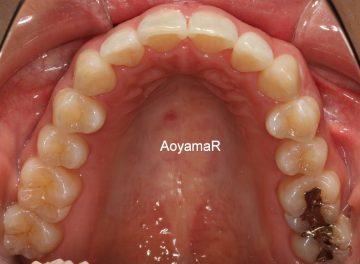

そう生(歯並びのガタガタ、乱杭歯、八重歯)の矯正症例

CASE 19

(31歳 女性 )

マウスピース型カスタムメイド矯正装置(インビザライン)単独による治療

治療前

治療後